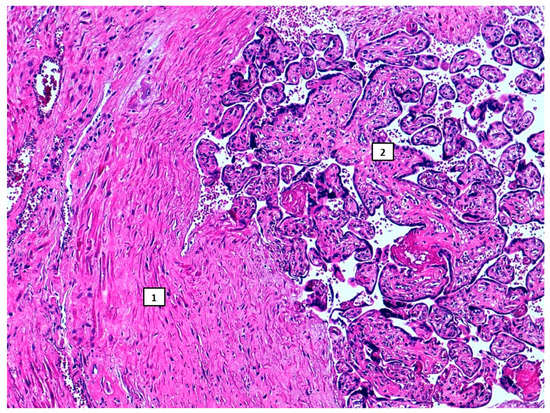

2. Case Report